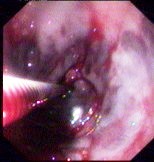

食管下段靜脈曲張出血 | 胃體後壁噴射狀出血 |

食管下段靜脈曲張出血

胃體後壁噴射狀出血